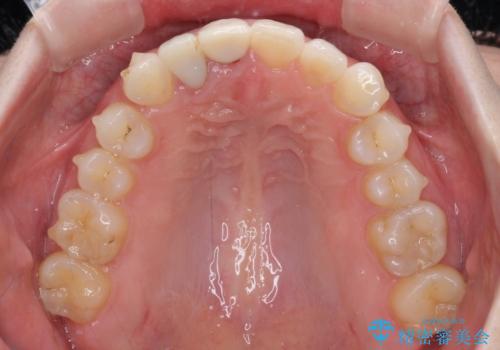

- 一度矯正治療を希望して始めたものの断念し、前歯をセラミッククラウンで治療した後に、やはり矯正でしっかり治したいとのことで来院された患者様です。

当初、前歯の歯列矯正を希望して銀座院に来院され、補助装置を装着するところまで進んだのですが断念してしまいました。

その後、他院で気になる前歯をセラミッククラウンで補綴治療をしたそうですが、やはり歯列を整えたいとのことで再度来院されました。

クラウンの状態は、根管治療の状態も含めて決して良い状態とは言えず、矯正治療後の根管治療と補綴治療の再治療を前提として、インビザラインによる矯正治療を行うこととしました。

治療前、下顎前歯はほとんど見えない咬み合わせでしたが、矯正治療によりディープバイトが改善されました。

矯正治療中に前歯2本のクラウンは外れてしまい、途中仮歯に替える必要があったので期間は掛かりましたが、歯列も整い、負担のかからない咬み合わせを達成することができました。